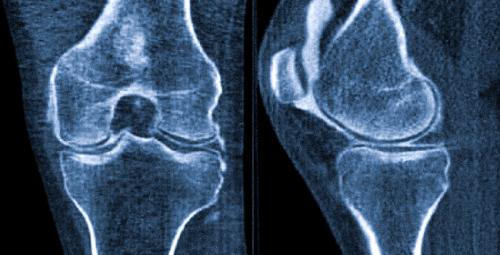

Как проявляются симптомы заболеваний костей и суставов

Заболевания костей и суставов – это медицинские проблемы, которые могут повлиять на структуру и функцию костей и суставов. Они могут быть вызваны различными факторами, такими как травмы, возраст, генетика, недостаточное питание и неправильный образ жизни.